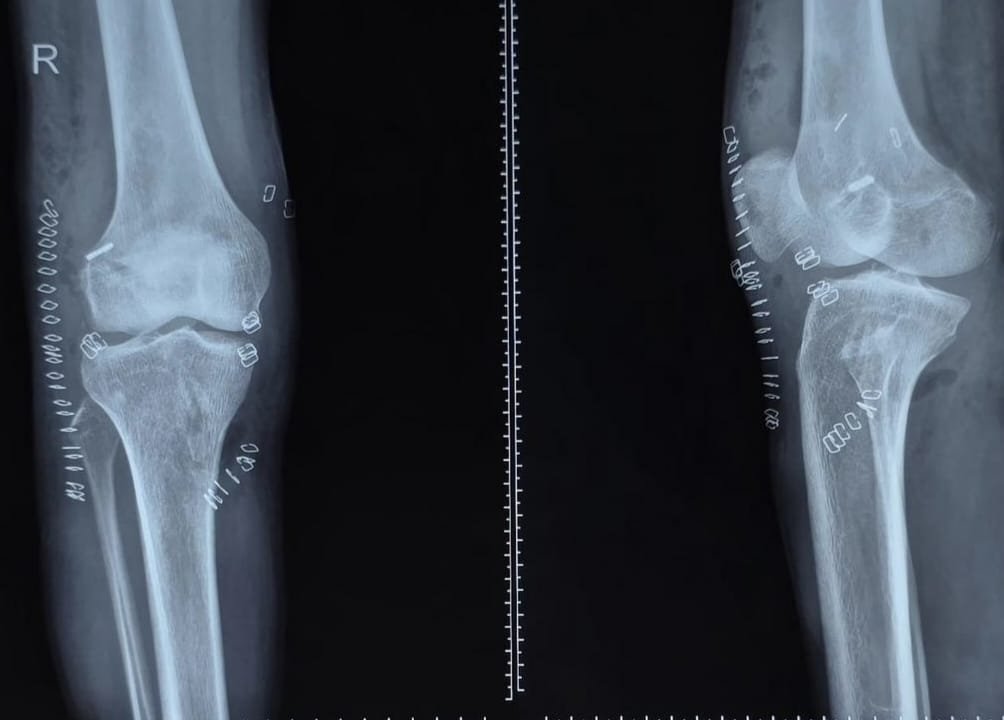

Knee Arthroscopy Surgery:

◆ ACL/PCL reconstruction

◆ Meniscus repair

◆ Multi-ligament knee injury management

◆ MPFL reconstruction

Joint Replacement (Robotic & Conventional):

◆ Total knee replacement